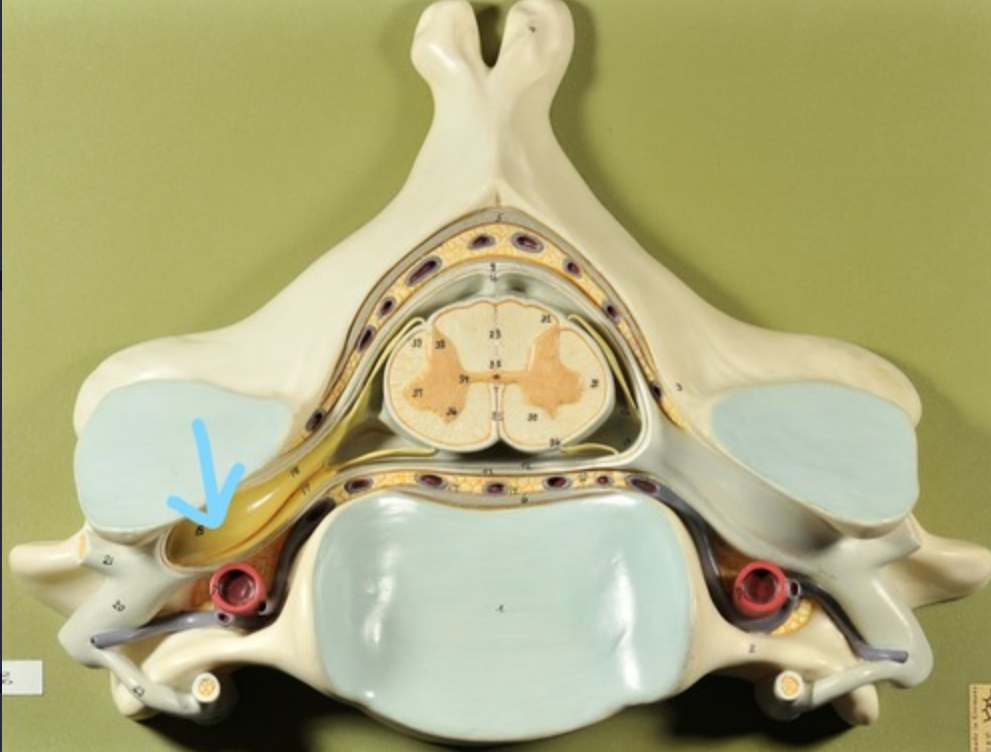

Spinal cord

Cauda equina

Dura mater (outermost layer)

White matter of spinal cord

Gray matter of spinal cord

Dorsal root ganglion

Dorsal root

Ventral root

Spinal nerve